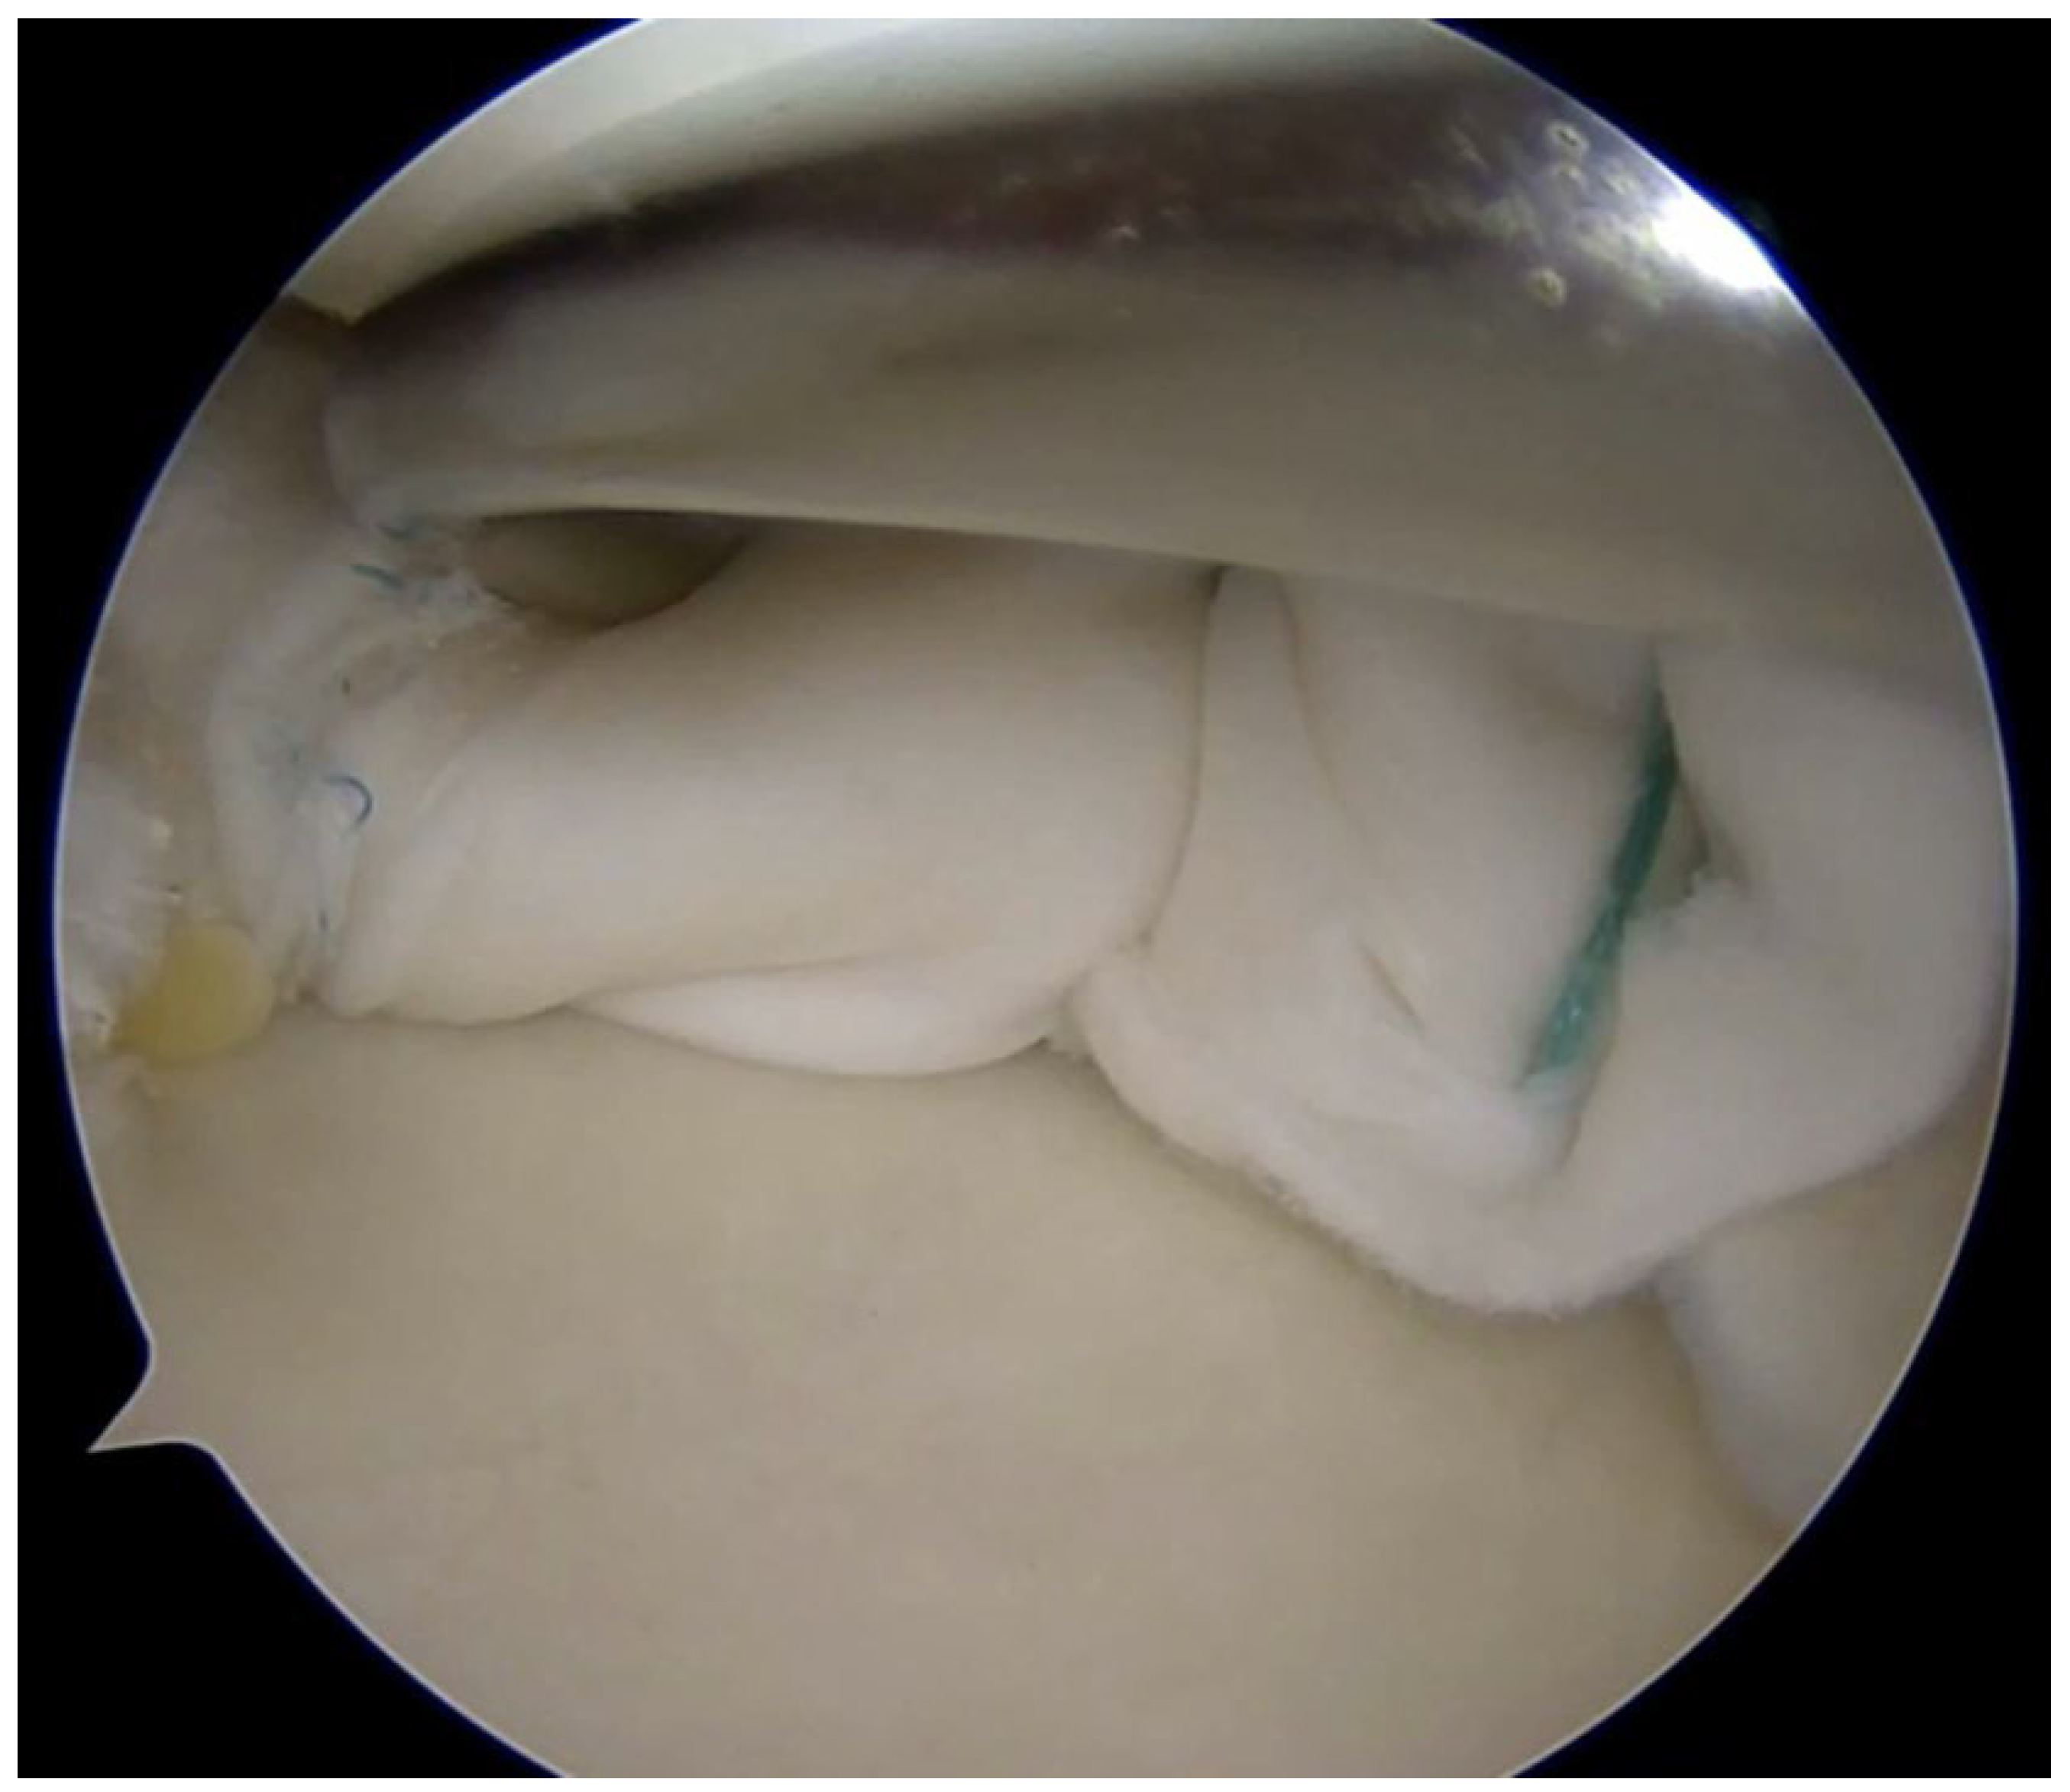

Coverage-based augmentation strategies combining a structural scaffold with biological stimulation have been proposed for the treatment of complex meniscal tears with limited intrinsic healing potential. Piontek et al. reported that Chondroguide collagen membrane—a bilayer, cell-free type I/III collagen scaffold originally developed for osteochondral repair—was “wrapped” around the meniscus tear site, followed by bone marrow injection resulted in significant clinical improvement and apparent structural healing in the majority of patients at 2-year follow-up, although the absence of a control group limits definitive conclusions [49,50]. Significant improvement in IKDC and Lysholm scores at 2-year follow-up were found. Follow-up MRI demonstrated no meniscal tear in 76% of the operated menisci [50]. Earlier work by Henning et al. demonstrated that fascial sheath coverage combined with exogenous fibrin clot injection improved healing rates in complex meniscal tears, supporting the concept that mechanical containment coupled with biologic augmentation can enhance repair [31]. The study reported improved healing rates from 75% to 92% for complex meniscal tears including double flap, double longitudinal, and radial tears when treated with fascia sheath coverage and fibrin clot, compared to conventional repair alone [31]. However, one important limitation is that despite the improved overall healing rate, tears in the middle one-third of the lateral meniscus still showed high failure rates even with this augmentation technique [31]. Together, these studies suggest that providing both structural stability and a biologically favorable microenvironment may expand repair indications for complex meniscal lesions; however, controlled comparative studies are needed to define efficacy and optimal indications (Figure 4).

Figure 4. Complex meniscus tears treated with collagen matrix wrapping.